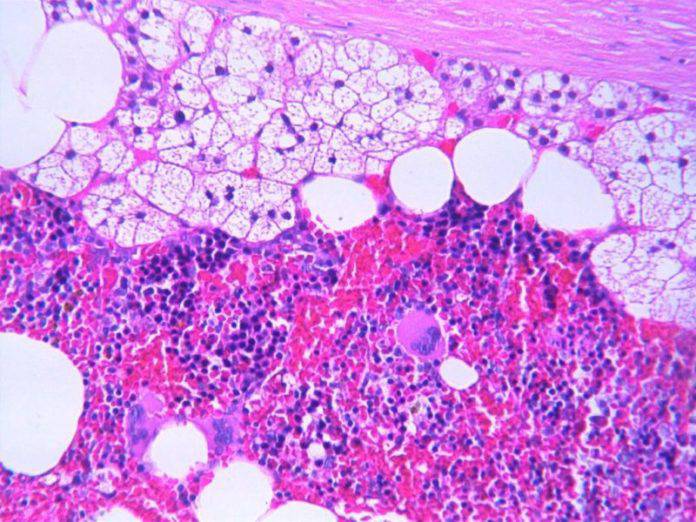

ดังนั้นหากมีตุ่มน้ำ หรือแผลถลอกตามตัว ควรมาพบแพทย์เพื่อตรวจเพิ่มเติม โดยโรคตุ่มน้ำพอง สามารถยืนยันการวินิจฉัยโดยการตรวจชิ้นเนื้อทางห้องปฏิบัติการและตรวจทางอิมมูโนเรืองแสง การรักษาหลักของโรคตุ่มน้ำพองจะเป็นการใช้ยากดภูมิ เพื่อหยุดไม่ให้ภูมิคุ้มกันของตนเองมาทำลายส่วนประกอบของชั้นผิวหนัง